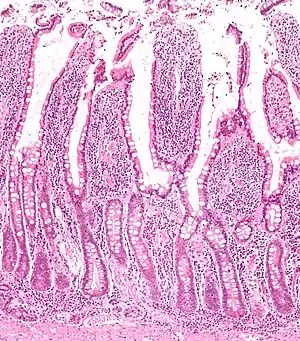

Micrograph of the small intestine mucosa showing the intestinal glands - bottom 1/3 of image. H&E stain.

In histology, an intestinal gland (also crypt of Lieberkühn and intestinal crypt) is a gland found in between villi in the intestinal epithelium lining of the small intestine and large intestine (or colon). The glands and intestinal villi are covered by epithelium, which contains multiple types of cells: enterocytes (absorbing water and electrolytes), goblet cells (secreting mucus), enteroendocrine cells (secreting hormones), cup cells, tuft cells, and at the base of the gland, Paneth cells (secreting anti-microbial peptides) and stem cells.

Intestinal glands are found in the epithelia of the small intestine, namely the duodenum, jejunum, and ileum, and in the large intestine (colon), where they are sometimes called colonic crypts. Intestinal glands of the small intestine contain a base of replicating stem cells, Paneth cells of the innate immune system, and goblet cells, which produce mucus.[1] In the colon, crypts do not have Paneth cells.[2]